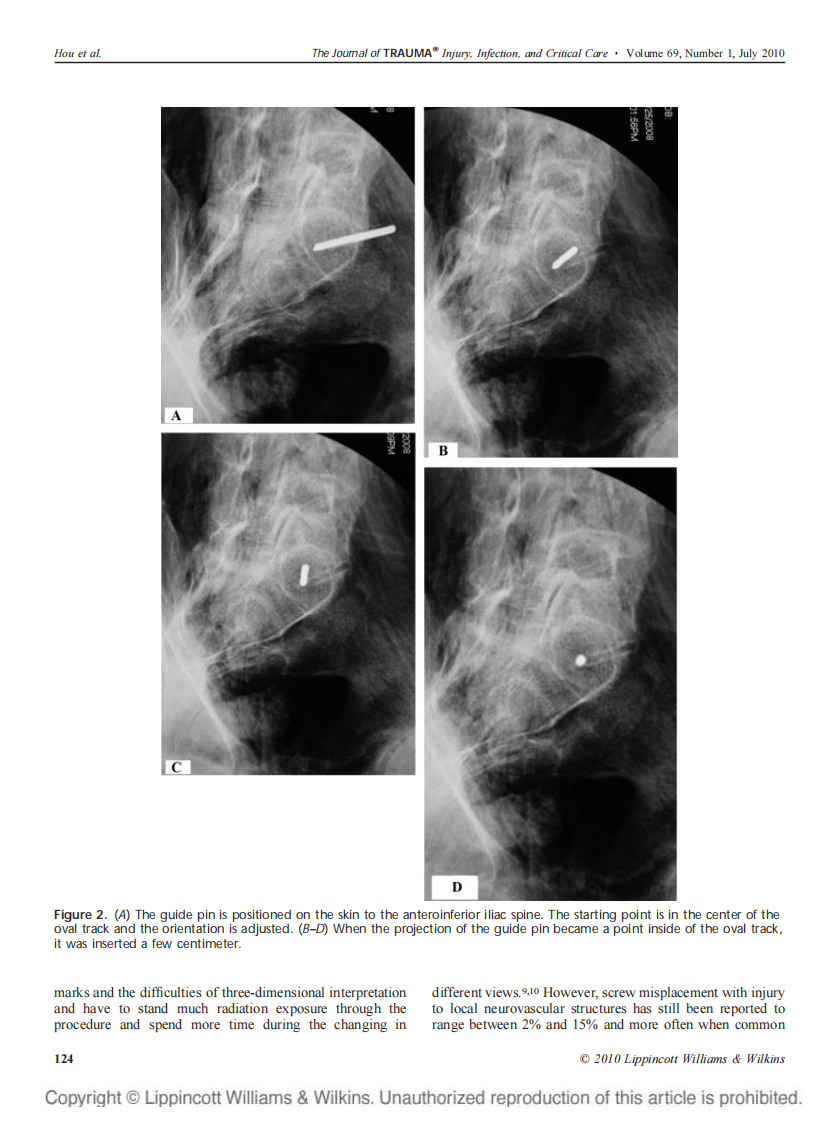

骶1椎弓根轴位 侯志勇.pdf